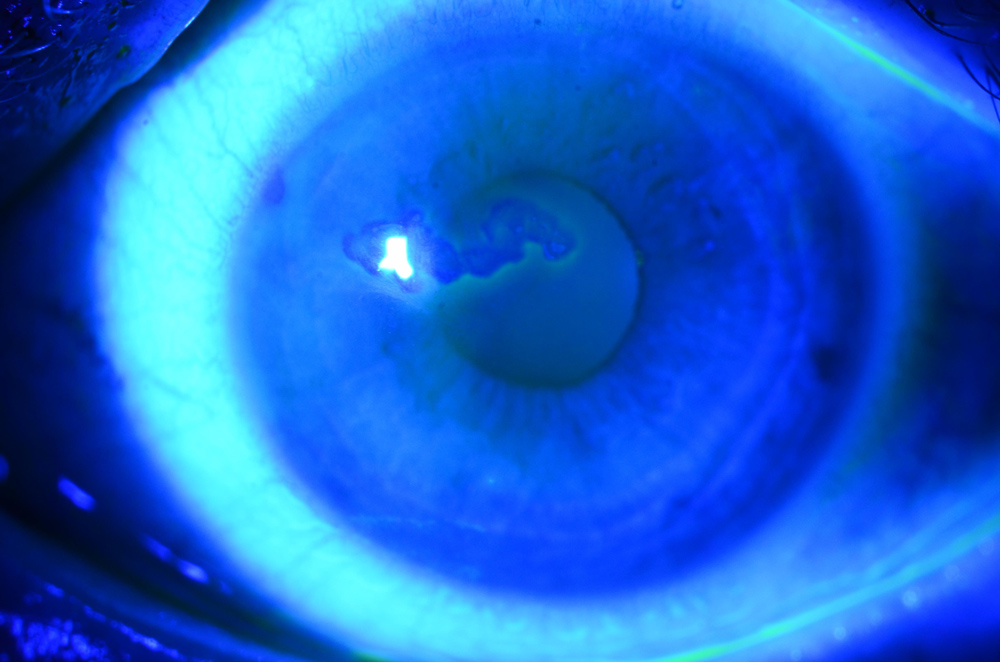

The best way to test for EBMD is by putting fluorescein in and looking for negative staining, he said, which is where the fluorescein runs off the high points in the cornea, and โthese little mountaintops stick out, and that causes the distortion of the vision.โ If you look hard enough, many patients have mild, typically peripheral, asymptomatic EBMD changes, but it is still important to know in case they develop symptoms in the future. Most of the time EBMD wonโt cause visual problems.

Source: Christopher J. Rapuano, MD